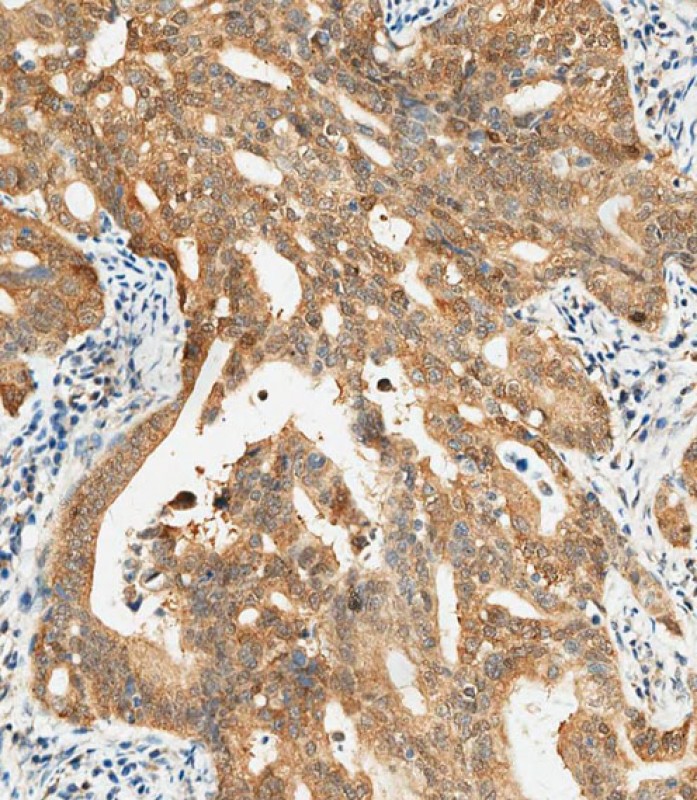

- P34592 staining CTAG1A in human gastric carcinoma tissue sections by Immunohistochemistry (IHC-P - paraformaldehyde-fixed, paraffin-embedded sections). Samples were incubated with primary antibody (1/250) for 1 hours at room temperature. A undiluted biotinylated goat polyvalent antibody was used as the secondary antibody.